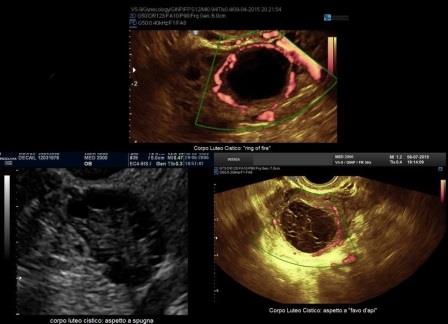

E' la localizzazione più frequente della patologia endometriosica rappresentando circa il 65% dei casi; gli aspetti ecografici più comuni delle cisti endometriosiche ovariche o endometriomi sono:

- cisti uniloculare o multiloculare con un massimo di 4 concamerazioni;

- contenuto "ground glass" ("a vetro smerigliato") legato all'accumulo di cellule ematiche che sfaldano dalla parete e di emosiderina;

- presenza di foci iperecogeni di parete;

- parete esterna della cisti spessa a superficie regolare;

- modesta vascolarizzazione di parete.

In un 35% dei casi gli aspetti degli endometriomi sono meno tipici:

- presenza di sottili setti intracistici che danno origine a cisti multiloculari;

- contenuto disomogeneo per la presenza di aree a differente ecogenicità, iperecogene o ipoecogene, legate ad un addensamento del contenuto cistico (sludge) o a coaguli;

- presenza di irregolarità di parete.

In questi casi sono di aiuto per una corretta diagnosi:

- il power doppler che consente di valutare la presenza di scarsa vascolarizzazione di parete e la assente vascolarizzazione delle aree di addensamento e delle irregolarità di parete;

- esercitando una lieve pressione con la sonda TV è possibile ricercare i movimenti delle strutture endocistiche (sludge e coaguli).

La diagnosi differenziale deve essere posta nei confronti di:

- tumori ovarici invasivi o borderline: questi possono avere un contenuto simile agli endometriomi ma sono frequentemente masse solide o multiloculari solide con papille ed aree solide vascolarizzate al Doppler;

- cistoadenomi mucinosi: possono avere un contenuto simile agli endometriomi ma sono spesso multloculari con setti sottili (< 5 mm.) e non possiedono i tipici spots iperecogeni di parete;

- cisti luteiniche: la diagnosi differenziale si basa sulla storia clinica della paziente con endometriosi (dismenorrea, infertilità) e sui differenti aspetti ecografici delle cisti luteiniche caratterizzate da una ricca vascolarizzazione di parete ("ring of fire") e da un contenuto endocistico "a spugna" o "a favo d'api" che si modifica nel giro di alcuni giorni.